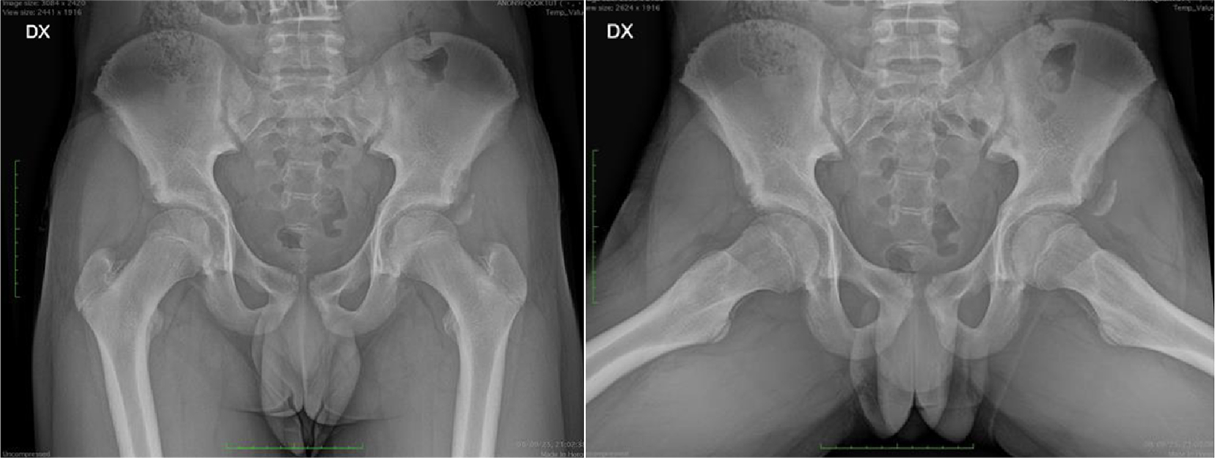

Fifty shades of grey

Caso condiviso da Marcello De Santis